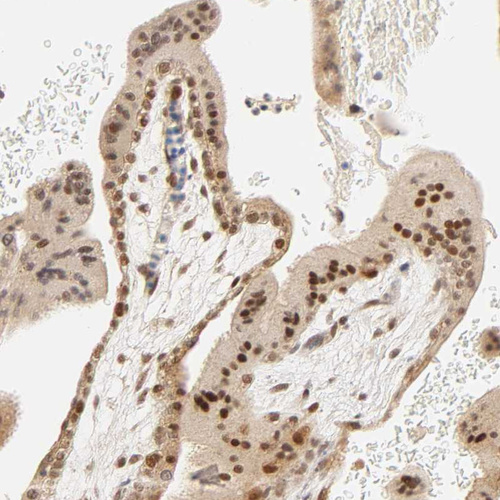

Immunohistochemical staining of human placenta shows moderate nuclear/cytoplasmic positivity in trophoblastic cells.